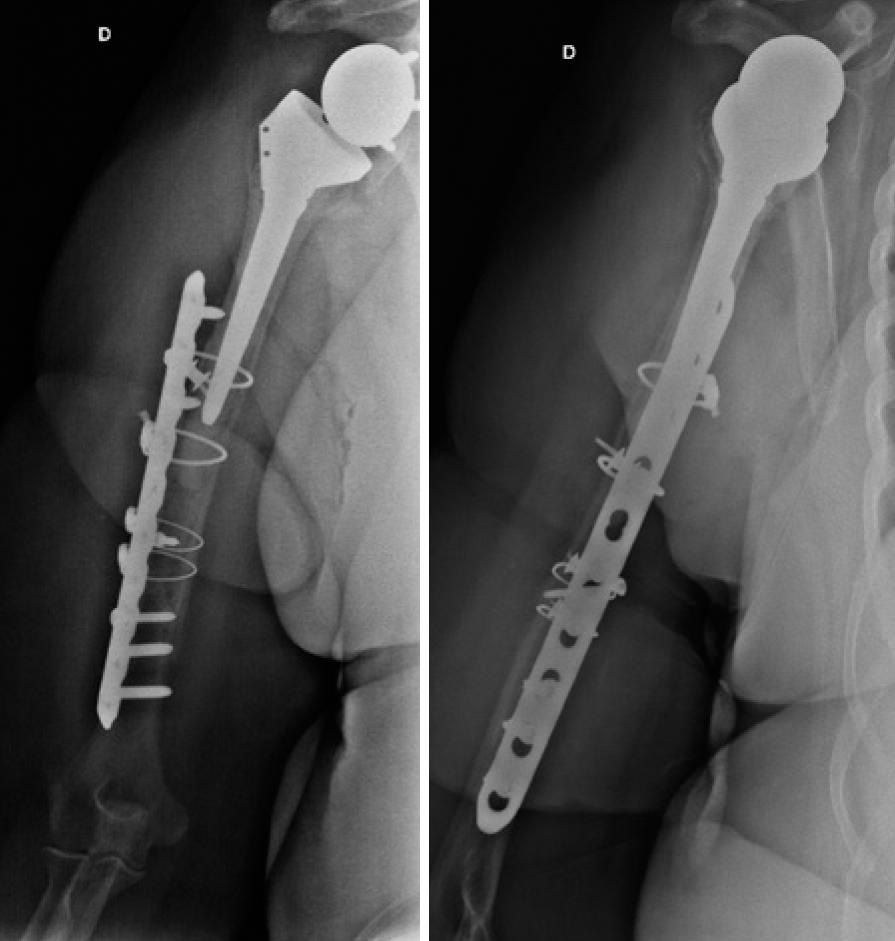

As fraturas periprotéticas do ombro representam uma grave complicação após a substituição da articulação. Devido ao rápido aumento do número de cirurgias de artroplastia reversa no ombro, as fraturas periprótese do úmero, descritas como raras, podem aumentar no futuro próximo. Descrevemos um caso de fratura desviada do úmero abaixo do componente umeral de uma artroplastia reversa. A paciente era uma mulher de 85 anos de idade, que tinha uma artroplastia reversa do ombro há 6 anos. O tratamento cirúrgico consistiu em osteossíntese com placa, parafusos e cerclagem. Os objetivos do presente trabalho foram reportar um caso inédito na literatura brasileira, e revisar a literatura existente e as classificações da lesão.